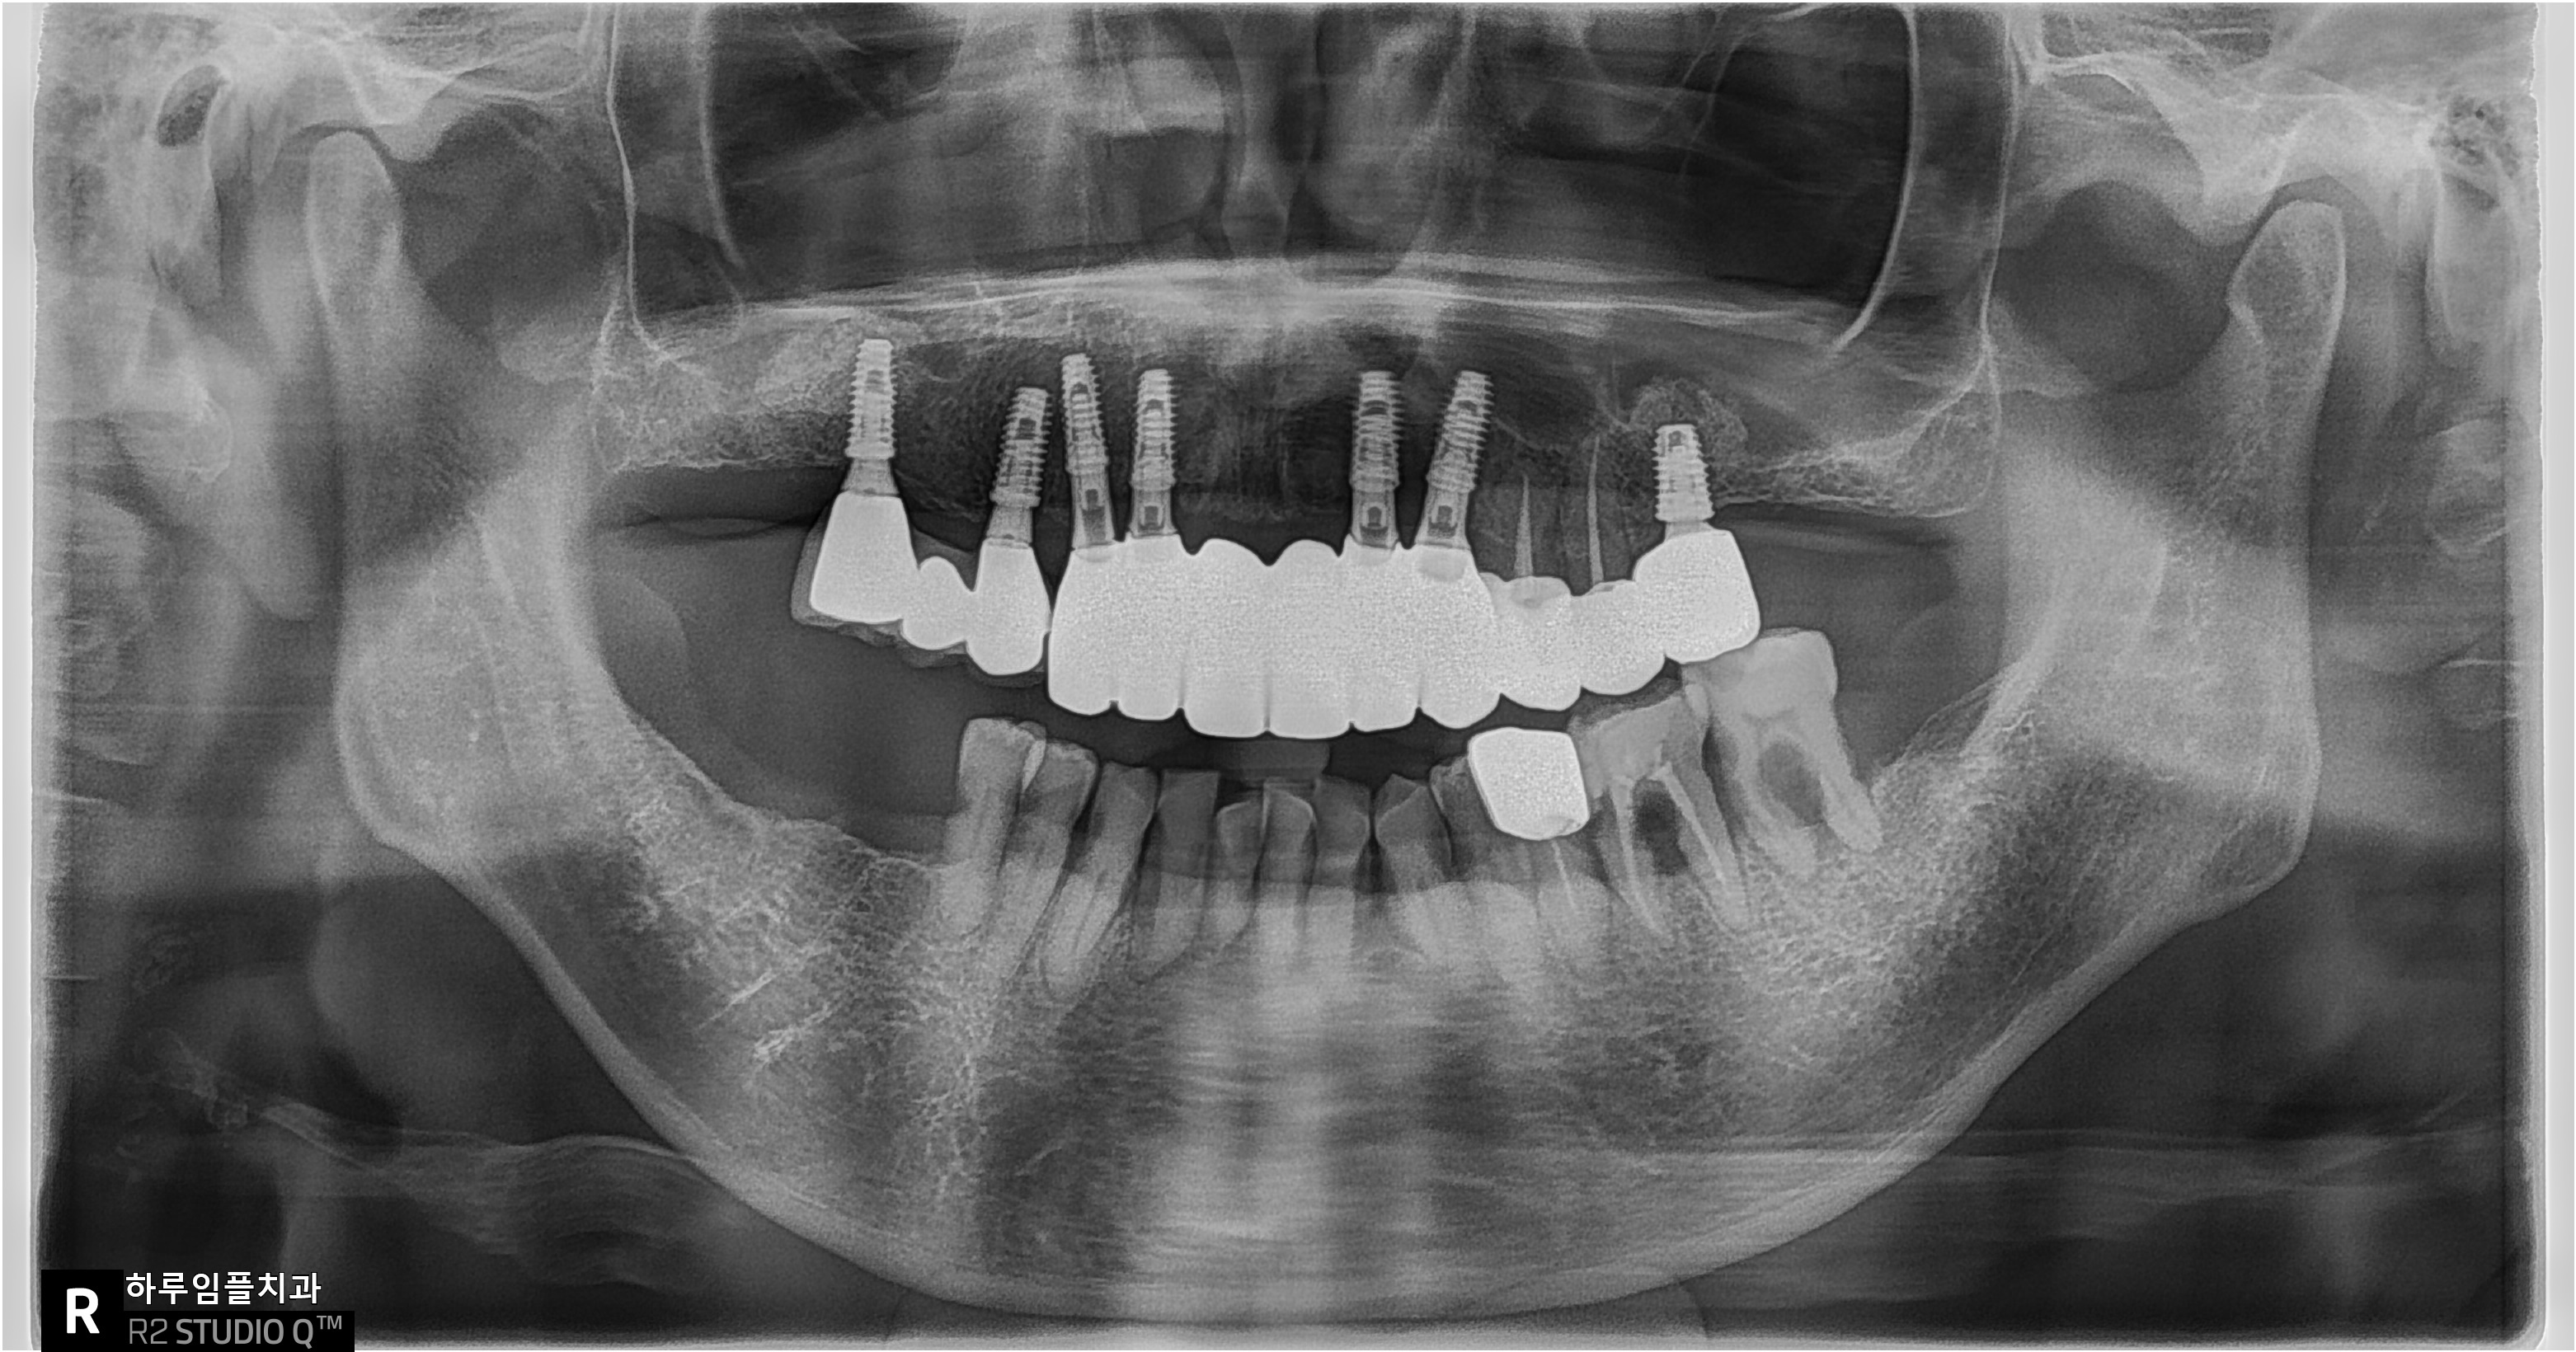

엑스레이를 찍어보니,

아래 앞니는 풍치로 인해

잇몸뼈가 많이 녹아 있었고

아래 어금니 쪽도

이미 뼈 흡수가 진행된 상태였습니다.

전체적으로 치아가 이제는

버티기 어려운 단계라고 할 수 있죠..